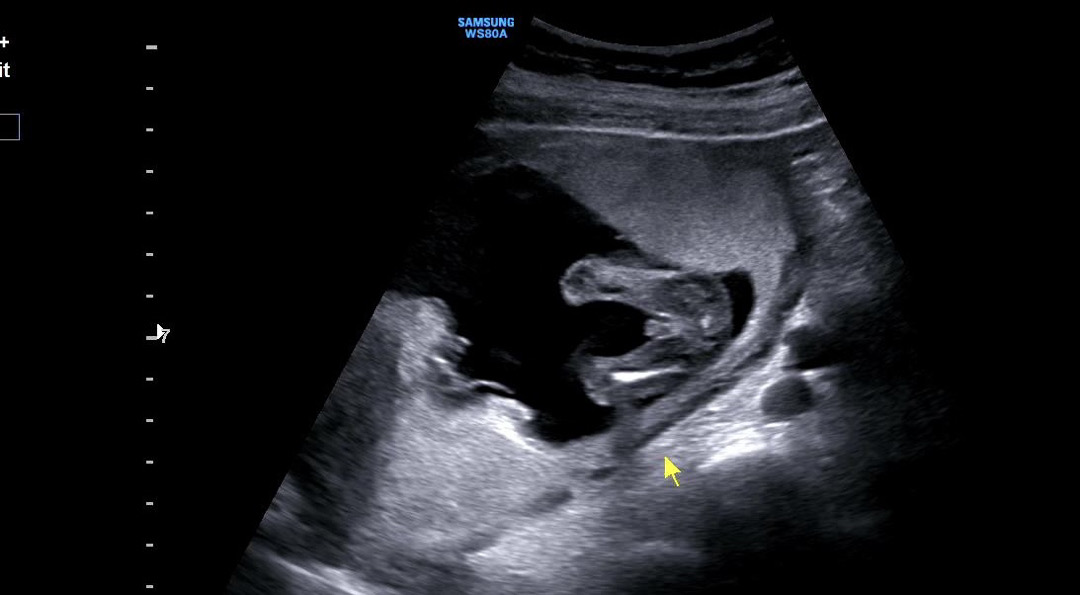

하 .. 암만봐도 🌶️인 것 같죠..? 의사쌤은 확실히는 모르겠지만 거의 아들인 것 같다고 하시기는 했거듴요.. 베동님들이 봐도 아들인 것 같나유 ㅠ